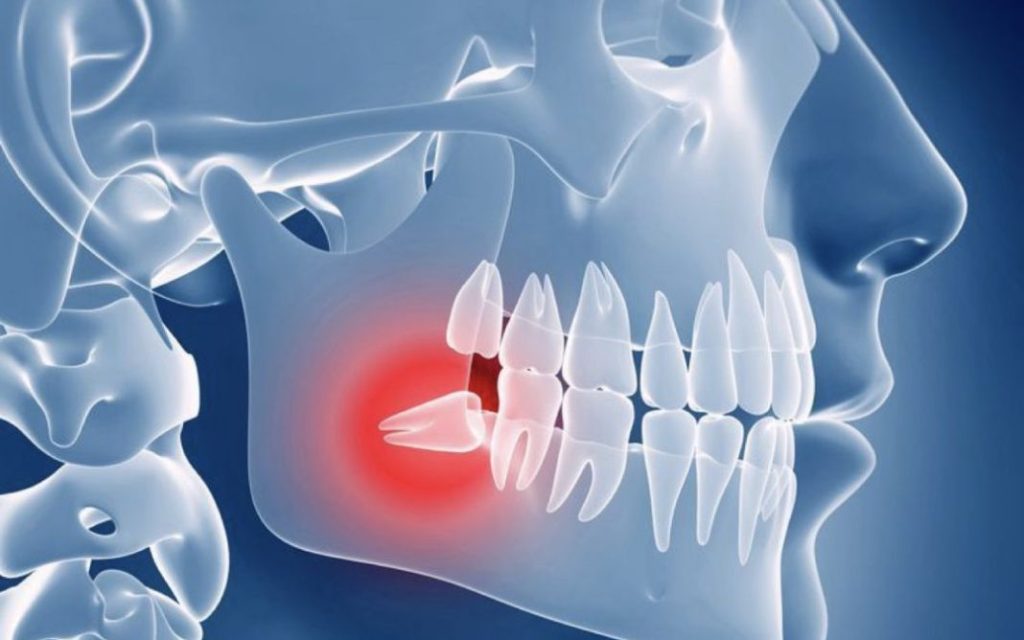

La aparición de las muelas del juicio puede provocar diversos problemas dentales. Debido a la falta de espacio en la mandíbula, las muelas del juicio pueden erupcionar parcial o completamente impactadas, es decir, que no pueden salir completamente de las encías.

Esto puede causar dolor, inflamación e infección. Además, las muelas del juicio también pueden ejercer presión sobre los dientes adyacentes, causando apiñamiento y desalineación dental.

Como resultado, muchas veces no hay suficiente espacio en la boca para que las muelas del juicio erupcionen correctamente. Esto puede causar que las muelas del juicio se impacten o queden atrapadas en el hueso o las encías, lo que puede ser doloroso e incluso causar infecciones.

Cuando las muelas del juicio no tienen suficiente espacio para salir, pueden quedar impactadas en la mandíbula o en las encías. Esto puede causar dolor, hinchazón, infecciones y daño a los dientes vecinos, lo que hace que la extracción sea necesaria en muchos casos. Las muelas del juicio impactadas también pueden causar la formación de quistes o tumores en el área afectada.